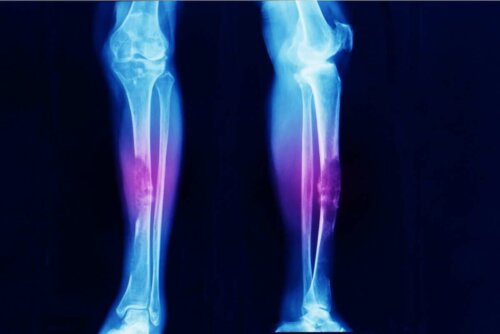

- Osteosarkooma on luusyöpä.

Sarkoomat eivät ole yleisiä. Useat tutkimukset itse asiassa osoittavat, että osteosarkooma (luustossa oleva kasvain) kattaa vain 0,2 % kaikista pahanlaatuisista kasvaimista. Tämä tarkoittaa sitä, että sen vuosittainen esiintyvyys on noin kolme tapausta miljoonaa ihmistä kohden.